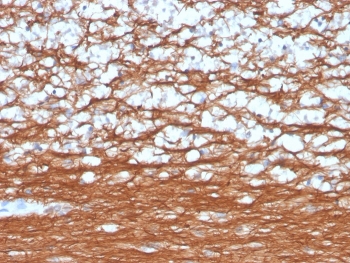

PGP9.5 Antibody / Neuroendocrine Tumor Marker Antibody. Immunohistochemistry analysis of PGP9.5 / UCHL1 in FFPE human cerebellum. IHC staining of FFPE human cerebellum using PGP9.5 Antibody / Neuroendocrine Tumor Marker Antibody demonstrates strong HRP-DAB brown cytoplasmic labeling of neuronal cells and extensive neuritic processes, reflecting the neuroendocrine-associated expression profile of UCHL1. The staining highlights dense neuronal networks that parallel expression patterns observed in neuroendocrine tumors, where PGP9.5 is commonly used as a tumor marker for identifying cells with neuroendocrine differentiation. Clone rUCHL1/4557 supports visualization of neuroendocrine-associated cellular features, with minimal staining in non-neuronal elements.